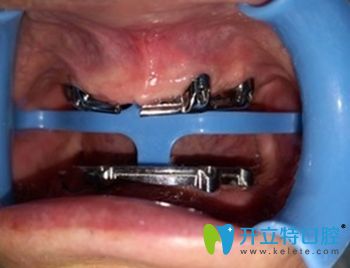

(老爸在鼎植口腔做種植牙的手術(shù)圖)   ↓

慈溪鼎植口腔種植牙術(shù)中照

做手術(shù)的是陳炳霖院長,還有一位謝醫(yī)生,聽說也是個(gè)醫(yī)學(xué)碩士。畢竟這么貴,要做一定得做好,醫(yī)生肯定是個(gè)關(guān)鍵。手術(shù)過程我們沒有在旁邊,這張圖片還是從門診電腦上拍的,這個(gè)工具好像叫導(dǎo)板還是啥名字。